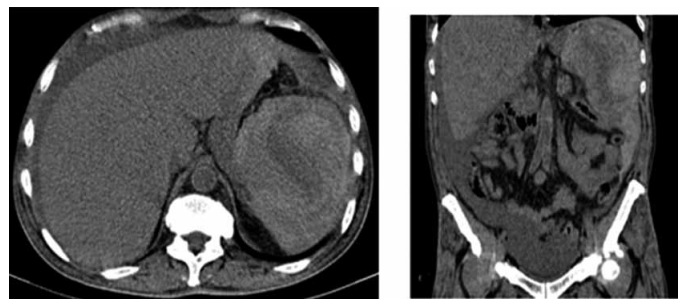

Homem de 39 anos é admitido no pronto-socorro com quadro de dor abdominal intensa no flanco esquerdo irradiando para o ombro homolateral (sinal de Kehr), associada a lipotimia e sudorese profusa, iniciada subitamente há cerca de 40 minutos. Nega trauma recente, esforço físico ou histórico de coagulopatia. Ao exame, encontra-se sudorético, com palidez cutaneomucosa importante, frequência cardíaca de 126 bpm, pressão arterial de 85/54 mmHg e dor à palpação profunda do hipocôndrio esquerdo, com sinais de irritação peritoneal. Os exames laboratoriais revelam:

• Hemoglobina: 7,4 g/dL (VN: 13,5–17,5)

• Hematócrito: 21% (VN: 41–53)

• Leucócitos: 14.500/mm³ com predomínio de neutrófilos

• Plaquetas: 250.000/mm³

• TAP e PTT normais

• Sorologias para mononucleose, citomegalovírus e hepatites negativas

A tomografia computadorizada de abdome está demonstrada a seguir:

(Coimbra, B. M.; Cardoso. T. T. Brad Cases - Brazilian Radiological Cases 2022, 1(4): 474-480)

Com base no quadro clínico, exames laboratoriais e de imagem, o diagnóstico e conduta para com o paciente são, respectivamente: